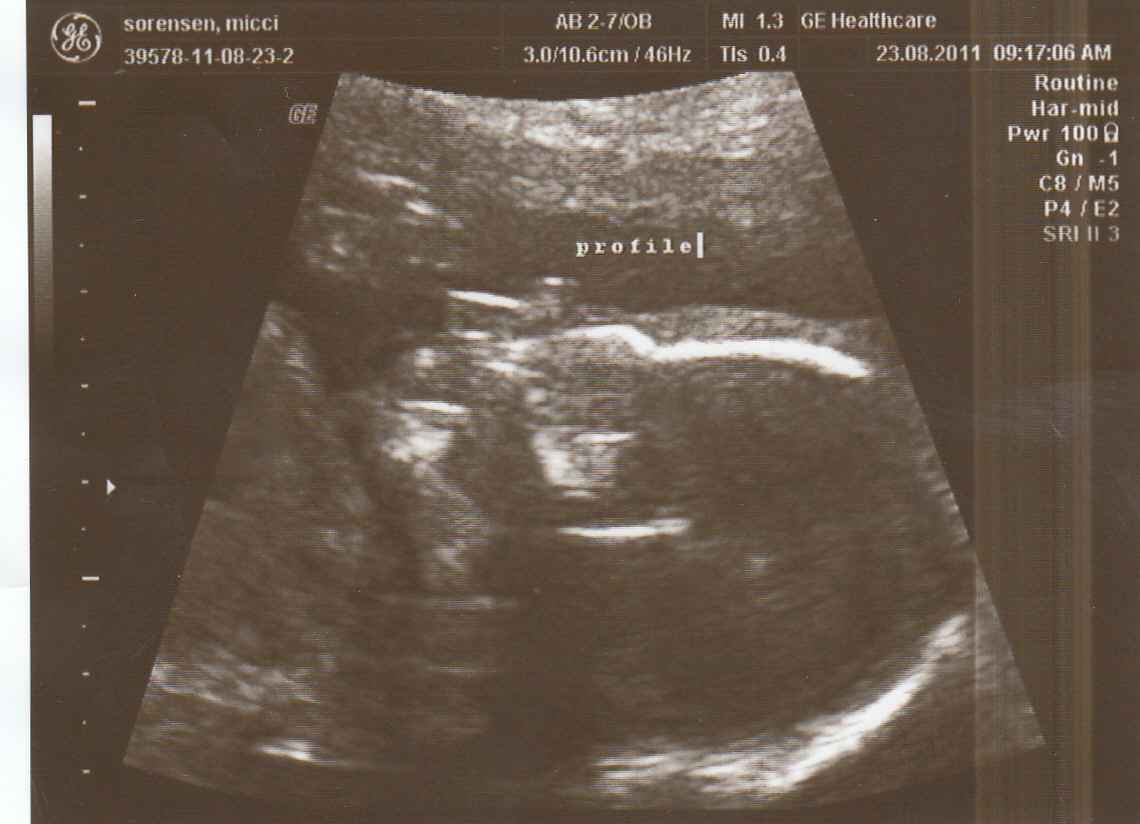

Turns out the baby is camera shy because the entire time we had the ultrasound, she/he would not uncross legs or give us a peek of ANYTHING. My doctor was like “Welp, sorry about that but it happens!” And I said NO FIX IT I CAN NOT WAIT ANY LONGER.

The great news is that the baby is measuring exactly on track- four chambers of the heart just working away, femurs are getting long and strong. Noggin is a good size, we saw ten tiny toes and a cute little hand. Baby is currently sitting transverse with its head to my left and its feet to my right. Estimated weight is 12 ounces….which is a can of soda.